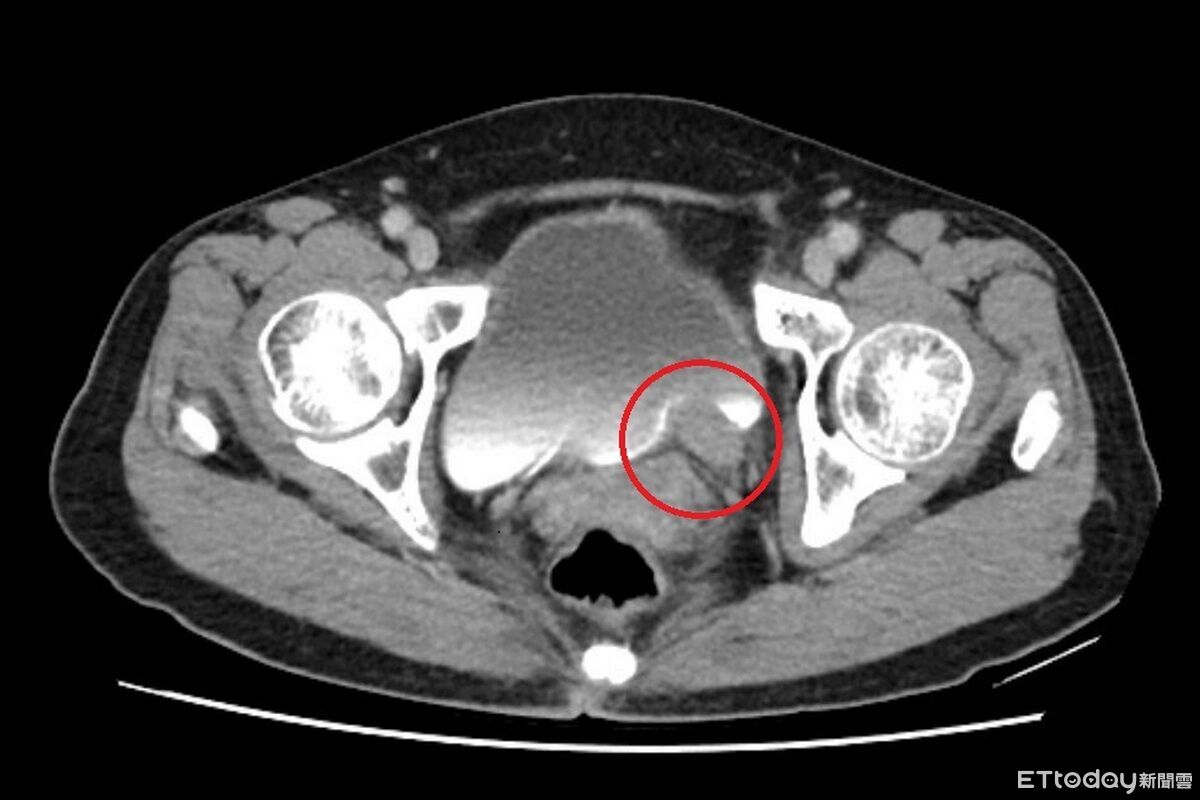

▲一名女性出現無痛性血尿,竟是輸尿管泌尿上皮癌。(圖/院方提供,下同)

67歲的林女士近期出現間歇性的無痛血尿,到醫院檢查發現左側輸尿管末端長了一顆5公分的腫瘤,且有腎水腫情形,確診為「輸尿管泌尿上皮癌」。醫師指出,長期吸菸、處於環境汙染及具家族史者都是危險因子,該癌症狀並不明顯,常見表現為無痛性血尿,若置之不理,腫瘤可能造成阻塞及腎衰竭、遠端轉移。

台北慈濟醫院泌尿科醫師許竣凱指出,輸尿管是連接腎臟與膀胱的重要管道,負責將腎臟產生的尿液順利輸送到膀胱儲存與排出,根據衛福部統計,泌尿上皮癌發生率每十萬人中約有40~50例,臨床上會以尿液檢驗、膀胱鏡、超音波與電腦斷層進行診斷,排除泌尿道感染、輸尿管結石等會伴隨疼痛的血尿後,就要高度懷疑腫瘤的可能。

許竣凱進一步舉例,以該案例來看,其腫瘤位於下段輸尿管,在化療成效良好的情況下,只需切除病灶,再將膀胱提起與輸尿管相接,完成重建,一般來說,若經完整切除,病人的五年存活率可達9成,但仍需定期追蹤,以降低復發風險。